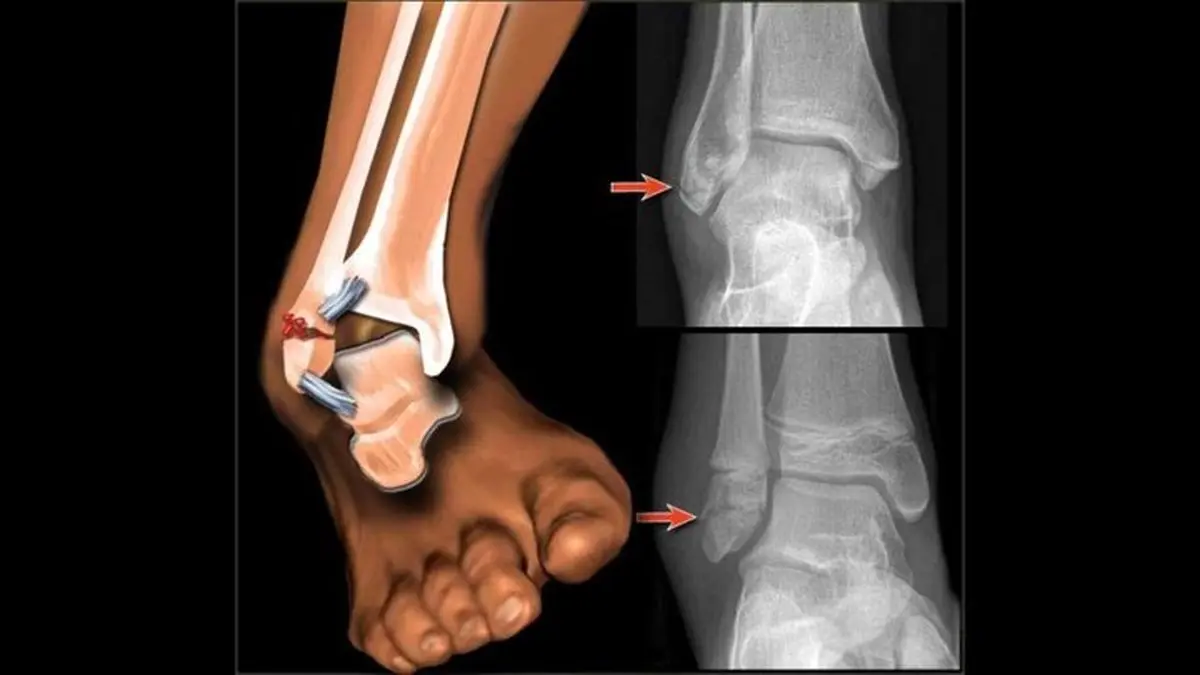

تشخیص شکستگی در صحنههای بحرانی، به دلیل وجود استرس، تاریکی، یا آسیبهای همراه متعدد، میتواند چالشبرانگیز باشد. علائم و نشانههای شکستگی استخوان بسته به ماهیت شکستگی (باز یا بسته، ساده یا مرکب)، میزان نیروی وارده، آستانه تحمل درد فرد مصدوم و وجود آسیبهای همزمان، میتواند متغیر باشد. با این حال، مجموعهای از علائم پایه وجود دارند که مشاهده آنها باید هشداری جدی برای احتمال شکستگی باشد:

۳. تغییر شکل غیرطبیعی عضو: اندام آسیبدیده ممکن است به شکل عجیبی کج، کوتاه یا پیچیده شده باشد و با اندام سالم تفاوت آشکاری پیدا کند.

۴. حرکت نابهجا و غیرطبیعی: در صورتی که شکستگی در محلی غیر از مفاصل رخ داده باشد، ممکن است مشاهده شود که بخشی از اندام در جهتی حرکت میکند که در حالت عادی نباید حرکت کند.

۵. تورم و کبودی: تجمع مایعات و خون در بافتهای اطراف محل شکستگی باعث تورم سریع میشود. همچنین تغییر رنگ پوست به سمت آبی مایل به بنفش (به دلیل خونریزی زیرپوستی) یک نشانه قوی است.

۷. نمایان شدن استخوان: در شکستگیهای باز، سر استخوان شکسته شده ممکن است از سطح پوست خارج شده و دیده شود.